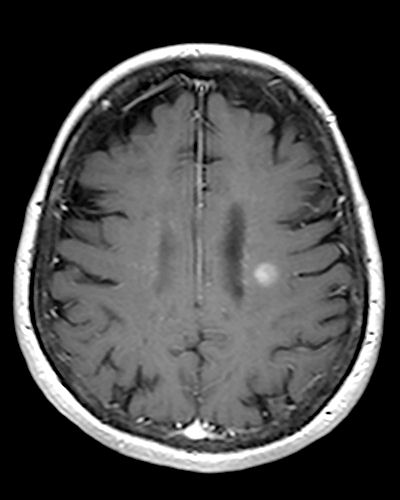

Mark the lesion in this T1 Gado scan